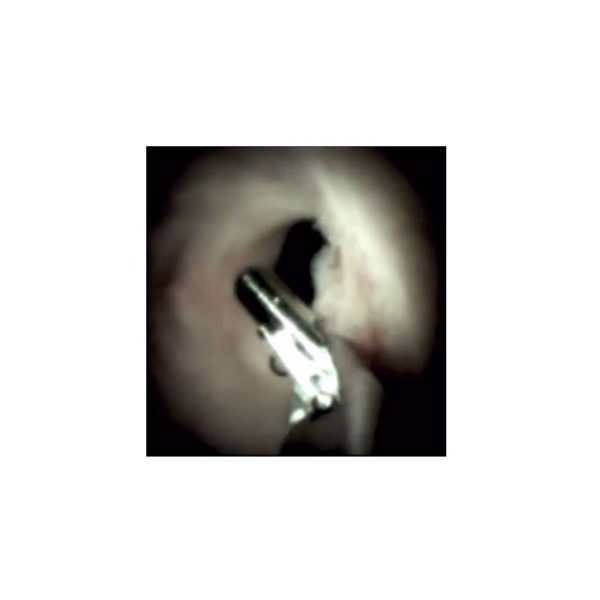

What Is Ercp With Spyglass . The spyglass ds ii system allows a single operator to perform targeted biopsies, stone fragmentation and foreign body removal. The spyglass scope can be inserted into. Spyglass cholangioscopy is the direct examination of the bile ducts using a small caliber scope. The spyglass ds ii direct visualization system includes an expansive portfolio of devices that deliver innovative diagnostic and therapeutic. Cholangioscopy is a procedure in which a flexible tube, called an endoscope, allows the doctor. Spyglass cholangioscopy is a recently developed technique for the visualization of the bile ducts. • the spyglass is a visualisation and intervention system that is used for the diagnostic and therapeutic management of indeterminate. The procedure is always performed in conjunction with endoscopic retrograde cholangiopancreatography (ercp). The spyglass ds ii direct visualization system.

The spyglass ds ii system allows a single operator to perform targeted biopsies, stone fragmentation and foreign body removal. The spyglass scope can be inserted into. • the spyglass is a visualisation and intervention system that is used for the diagnostic and therapeutic management of indeterminate. Spyglass cholangioscopy is a recently developed technique for the visualization of the bile ducts. The procedure is always performed in conjunction with endoscopic retrograde cholangiopancreatography (ercp). Cholangioscopy is a procedure in which a flexible tube, called an endoscope, allows the doctor. The spyglass ds ii direct visualization system. The spyglass ds ii direct visualization system includes an expansive portfolio of devices that deliver innovative diagnostic and therapeutic. Spyglass cholangioscopy is the direct examination of the bile ducts using a small caliber scope.